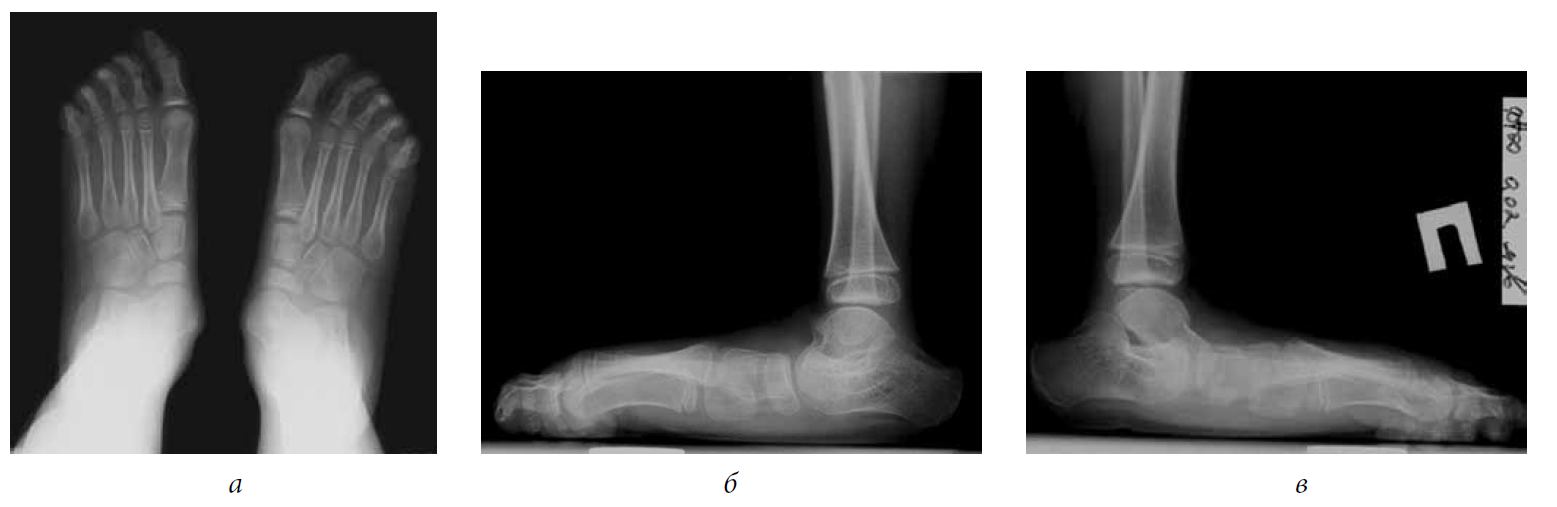

The surgery to eliminate TEPV was performed (Strayer surgery, subtalar arthroereisis, transposition with tenodesis of the anterior tibial muscle tendon under the navicular bone, grafting of the capsule of the talo-navicular joint). A cylinder plaster cast was applied from the upper third of the thigh to the tips of the toes. After 2 weeks, vertical orientation with a partial load in a plaster cast was allowed, 4 weeks after the plaster cast was removed, and a rehabilitation course was started. After 2 years and 6 months, the subtalar implants were removed (Fig. 3, 4).

Fig. 3. Radiographs of the feet under load 2 years and 6 months after surgery (lateral views)

Fig. 4. Radiographs of the feet under load 1 year after the removal of implants (lateral views)